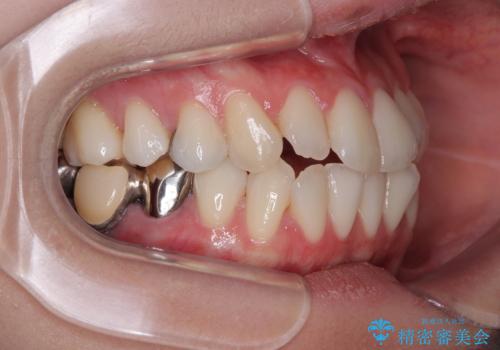

下顎臼歯部にブリッジが装着されており、移動不可のため、IPR(歯と歯の間を削る)と歯列全体を拡大させることで、歯並びを整えていくこととしました。

インビザライン特有の奥歯の噛みにくさが治療後半に発現しましたが、無事に終了させることができました。